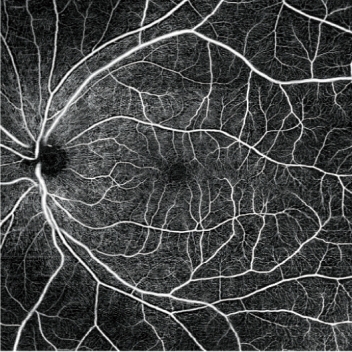

血流密度圖和灌注密度圖

量化每層血管后,可提供評估疾病進展和治療效果的指標。可使用血流密度圖和灌注密度圖進行量化分析。

灌注密度圖

血流密度圖

圖片由千葉大學醫學部附屬醫院、東北大學提供